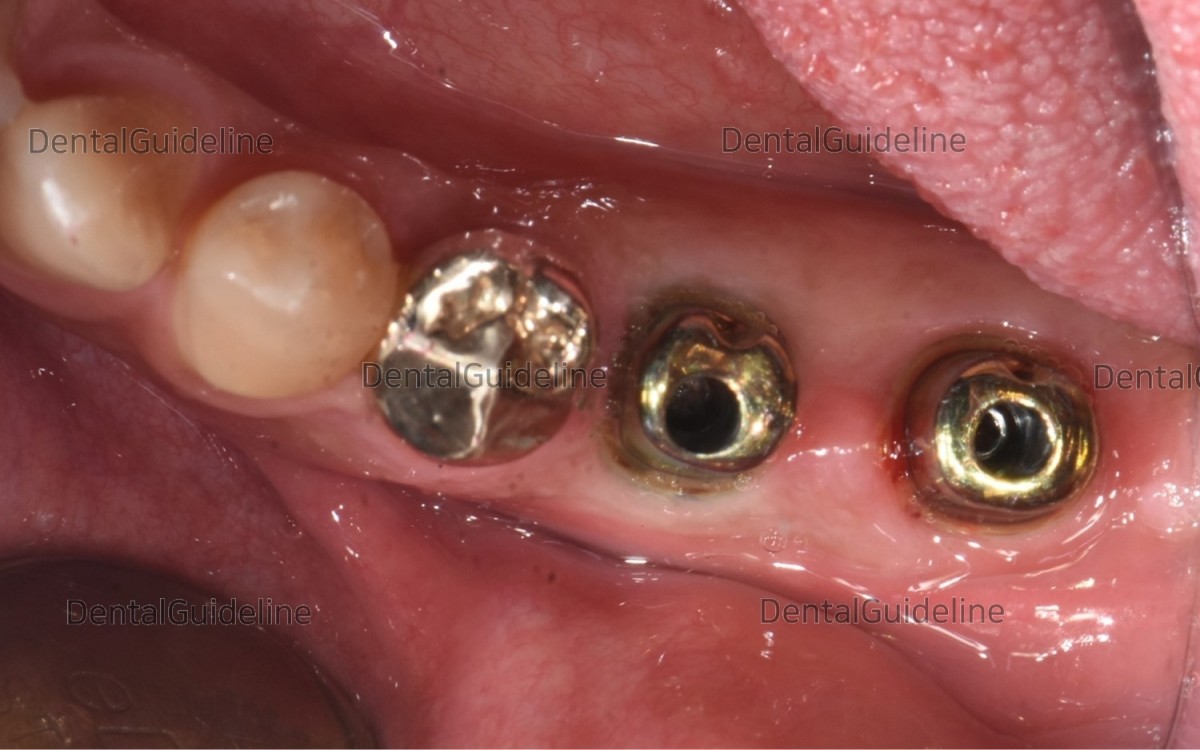

Intra-oral view and fractured tooth.

Intra-oral view on the day of implant placement (13 weeks after future site development).

Abutments were connected to the fixture.